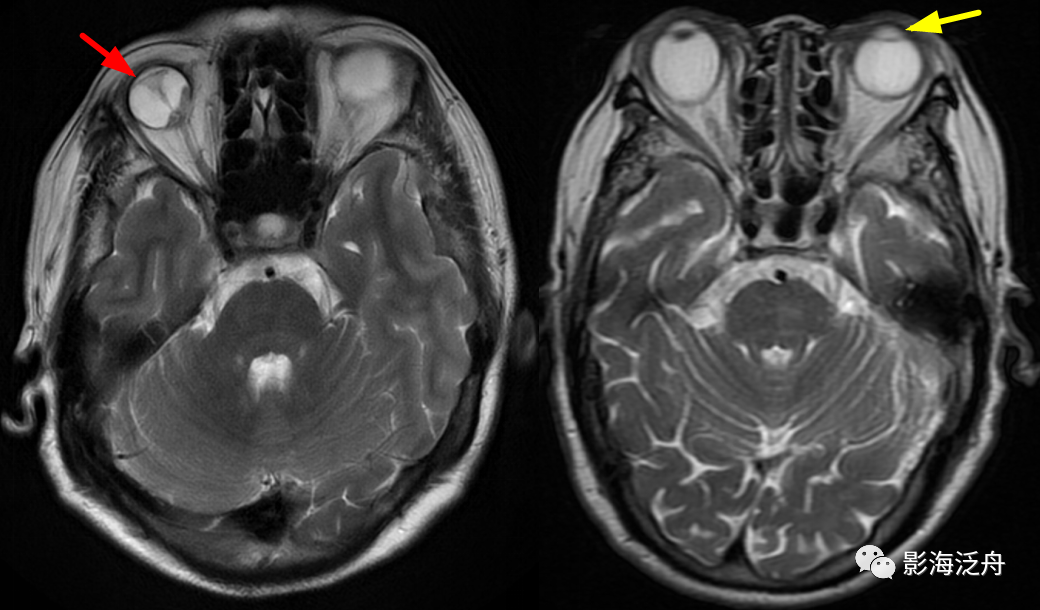

眼耳鼻喉病变

右侧为视网膜剥脱(红箭),眼球后部为剥离的视网膜组织及积血区;左侧为白内障

患者,T2WI上患眼晶状体信号均匀增高为其特征性表现。

左侧乳突

炎(红箭),右侧乳突气化良好,不含炎症,在MR上呈无信号(绿箭)。

部分患者的乳突窦气化不佳或者邻近颞骨外侧部过厚且黄骨髓较多时,可以在T2WI上呈高信号,尤其是两侧乳突发育不对称时很容易误诊为乳突炎。注意右侧粗大的流空血管影(绿箭)为颈内静脉。